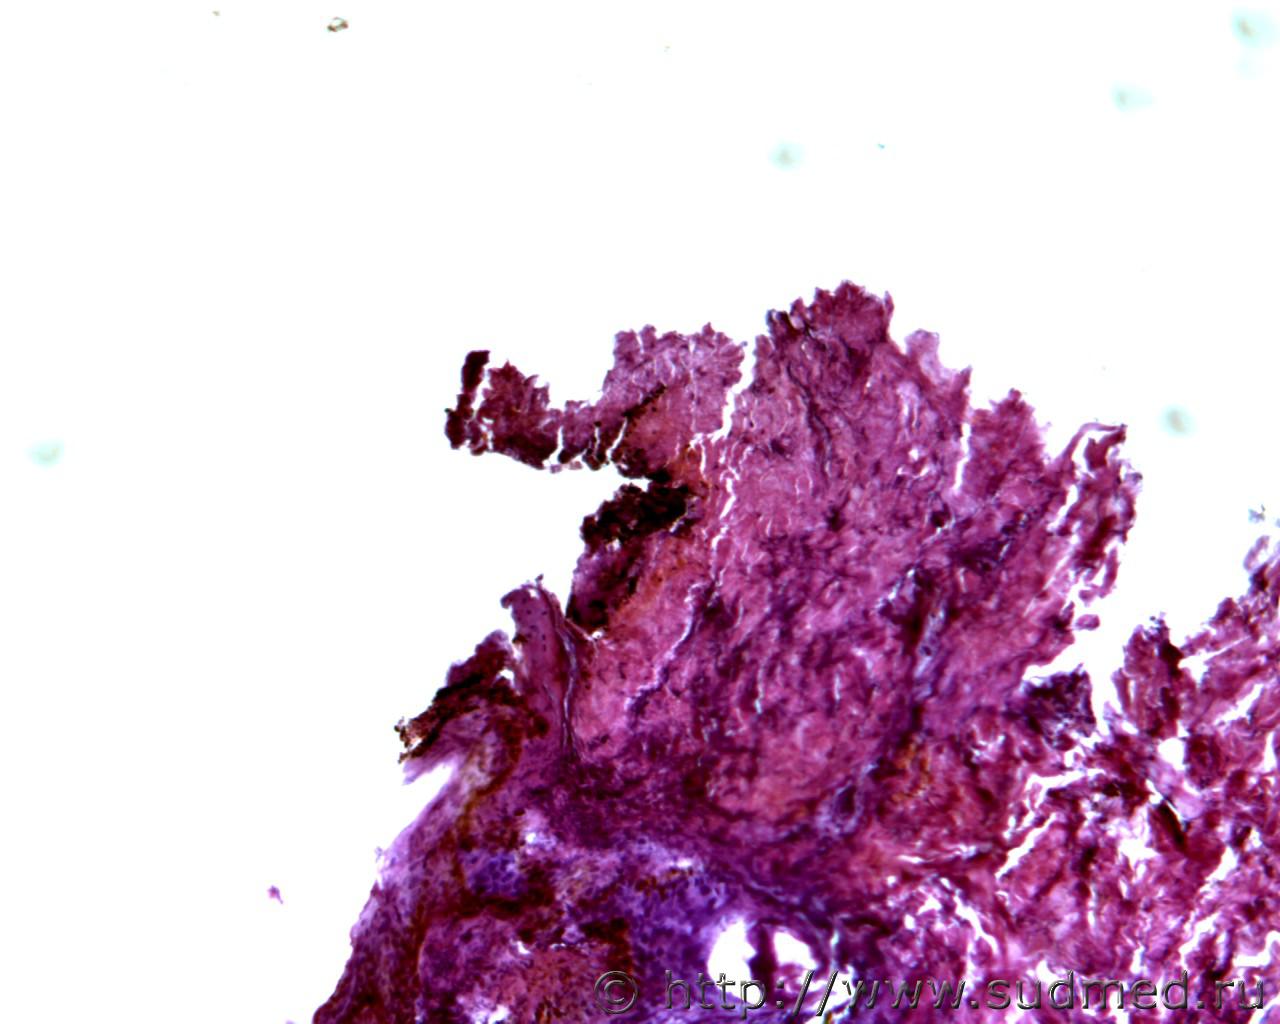

Копоть в крае входной огнестрельной пулевой раны.